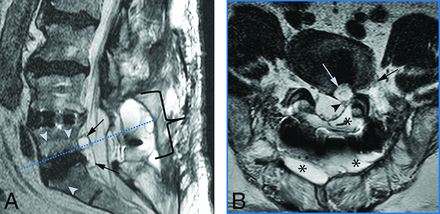

Most commonly, the formation of epidural cysts resulted in mass effect on the lateral recess of the descending nerve roots at the level of the intervertebral rhBMP-2 graft, which was identified in 5 patients (patients 2, 6, 7, 14, and 16). Among these, patient 14 demonstrated epidural cystic collections, extending from L5-S1 along the surgical corridor 60 days after combined extreme and posterior lumbar interbody fusion (XLIF + PLIF) of L4–S1 with laminectomy (Fig 3). The patient developed a new left foot drop and was diagnosed with an L5 radiculopathy with active denervation by electrophysiology. However, conservative management was successful, and the symptoms subsided. The cysts nearly resolved on the follow-up study 79 days later.

MR images in a 58-year-old man 2 months following BMP-augmented combined extreme lateral and posterior lumbar interbody fusion with laminectomy of L4–S1 and new-onset left foot drop. A, Sagittal T2-weighted MR image shows a lobulated epidural cyst at L5–S1 dorsal to the BMP graft (black arrows), endplate edema signal of the adjacent endplates (arrowheads), and the laminectomy defect with seroma formation (bracket). B, Axial T2-weighted MR image at L5–S1 (dashed blue line, A) demonstrates the left subarticular, epidural cyst (white arrow) adjacent to the BMP graft, abutting the left descending S1 nerve root (arrowhead) and the left exiting L5 nerve root (black arrow). Concomitant seroma is present and fills the laminectomy defect (asterisks).

Patients 2, 6, 7, and 14 presented with varying degrees of lumbosacral radiculopathy that was treated with epidural injections but did not require revision surgery. For these patients, a correlating single-level cyst located within the ventrolateral epidural space was observed on L-spine MR imaging postoperatively, exerting mild mass effect on the traversing L5 or S1 nerve roots.